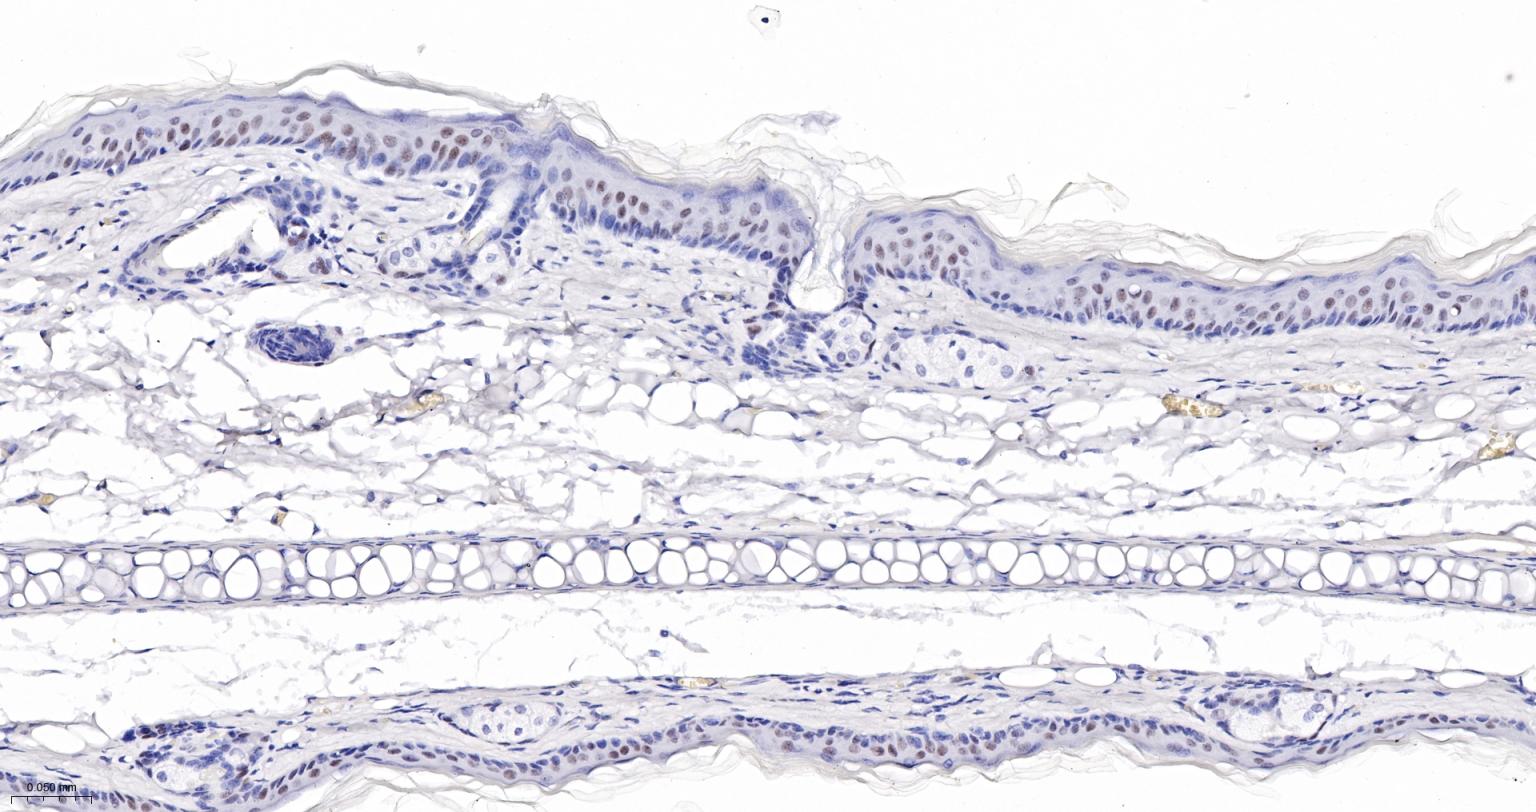

Paraformaldehyde-fixed, paraffin embedded Human Skin; Antigen retrieval by boiling in sodium citrate buffer (pH6.0) for 15 min; The section was incubated with Ctip2 Monoclonal Antibody, Unconjugated (bsm-61400R) at 1:200 overnight at 4°C, followed by conjugation to the bs-0295G-HRP and DAB (C-0010) staining.